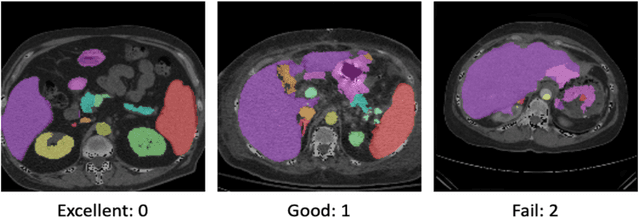

Abstract:Human in-the-loop quality assurance (QA) is typically performed after medical image segmentation to ensure that the systems are performing as intended, as well as identifying and excluding outliers. By performing QA on large-scale, previously unlabeled testing data, categorical QA scores can be generatedIn this paper, we propose a semi-supervised multi-organ segmentation deep neural network consisting of a traditional segmentation model generator and a QA involved discriminator. A large-scale dataset of 2027 volumes are used to train the generator, whose 2-D montage images and segmentation mask with QA scores are used to train the discriminator. To generate the QA scores, the 2-D montage images were reviewed manually and coded 0 (success), 1 (errors consistent with published performance), and 2 (gross failure). Then, the ResNet-18 network was trained with 1623 montage images in equal distribution of all three code labels and achieved an accuracy 94% for classification predictions with 404 montage images withheld for the test cohort. To assess the performance of using the QA supervision, the discriminator was used as a loss function in a multi-organ segmentation pipeline. The inclusion of QA-loss function boosted performance on the unlabeled test dataset from 714 patients to 951 patients over the baseline model. Additionally, the number of failures decreased from 606 (29.90%) to 402 (19.83%). The contributions of the proposed method are threefold: We show that (1) the QA scores can be used as a loss function to perform semi-supervised learning for unlabeled data, (2) the well trained discriminator is learnt by QA score rather than traditional true/false, and (3) the performance of multi-organ segmentation on unlabeled datasets can be fine-tuned with more robust and higher accuracy than the original baseline method.